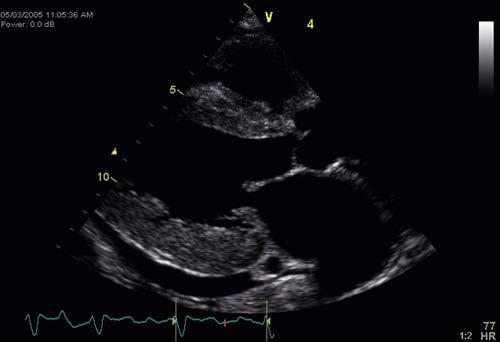

FIGURE 1-9 A, Ultrasound sent through a thin pie-slice–shaped volume of tissue produces an image commonly called a sector image or sector scan B, Sector scan of adult heart.